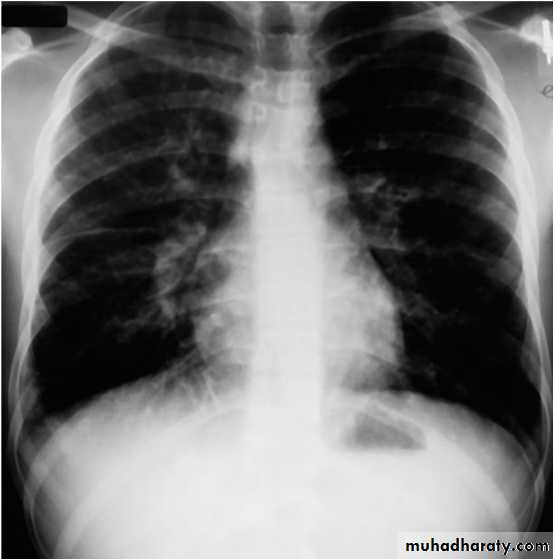

Mycoplasma pneumoniae infection (atypical pneumonia)

Atypical pneumonia, such as with M. pneumoniae and C. pneumoniae, shows increased interstitial markings or bronchopneumonia.